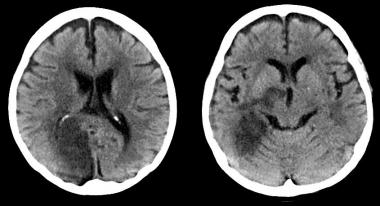

¿Por qué hay pacientes con ACV isquémico que no reciben tratamiento con tPA intravenoso?

En una gran cohorte de EEUU, una cuarta parte de los pacientes con accidente cerebrovascular isquémico e indicación para tPA-IV no recibieron la medicación. Se asoció con edad avanzada y con el sexo femenino, entre otros factores. Neurology, 14 de septiembre de 2016